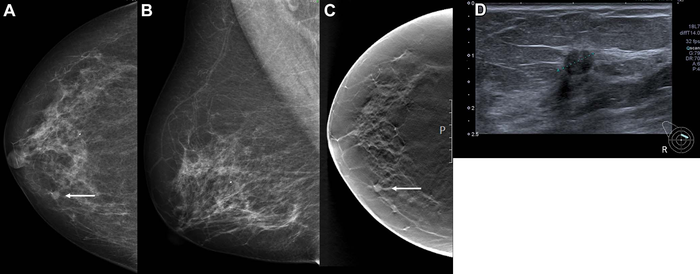

The dataset included 752 cancers detected at screening and 205 interval cancers, or cancers detected between screening rounds. The AI system predicted the risk of cancer on a scale from 1 to 10, with 1 representing the lowest risk and 10 the highest risk. A total of 87.6% (653 of 752) of screen-detected and 44.9% (92 of 205) of interval cancers had the highest AI score of 10.

The researchers created three thresholds to assess the performance of the AI system as a decision-making tool. Using a threshold that mirrors the average individual radiologist rate of positive interpretation, the proportion of screen-detected cancers not selected by the AI system was less than 20%. While the AI system performed well, the study’s reliance on retrospective data means that more research is needed.

The results showed favorable histopathologic characteristics associated with a better prognosis for screening-detected cancers with low versus high AI scores. Opposite results were observed for interval cancers. This may indicate that interval cancers with low AI scores are true interval cancers not visible on the screening mammograms.

The high percentage of true negative examinations classified with a low AI score has the potential of substantially reducing the interpretive volume, while allowing only a small proportion of cancers to go undetected. By using AI as one of the two readers in a double reading setting, the radiologist could still identify these cancers, the researchers said.